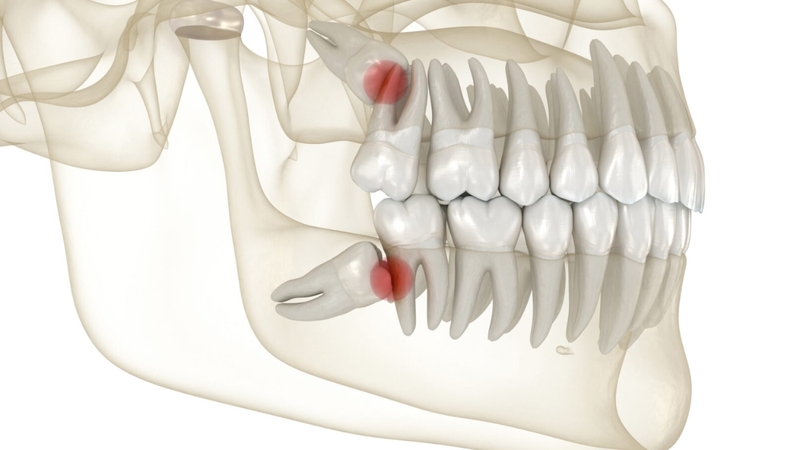

Răng khôn mọc lệch là tình trạng răng số 8 mọc sai hướng, không đúng vị trí do thiếu chỗ trên cung hàm. Răng có thể mọc nghiêng, đâm vào răng bên cạnh hoặc lệch ra má, gây đau nhức, viêm nướu, sâu răng và ảnh hưởng sức khỏe răng miệng nếu không được xử lý kịp thời.

Răng khôn mọc lệch là hiện tượng răng số 8 không có đủ khoảng trống để mọc thẳng, khiến chúng đâm vào răng bên cạnh hoặc mô mềm

Theo các chuyên gia nha khoa, răng khôn thường xuất hiện ở độ tuổi từ 17 đến 25, khi cung hàm đã phát triển đầy đủ, nhưng không phải ai cũng có đủ không gian cho răng khôn mọc đúng vị trí. Tình trạng này phổ biến đến mức, theo thống kê từ Bệnh viện Răng Hàm Mặt Trung ương, khoảng 70% người trưởng thành gặp phải ít nhất một răng khôn mọc lệch cần can thiệp.